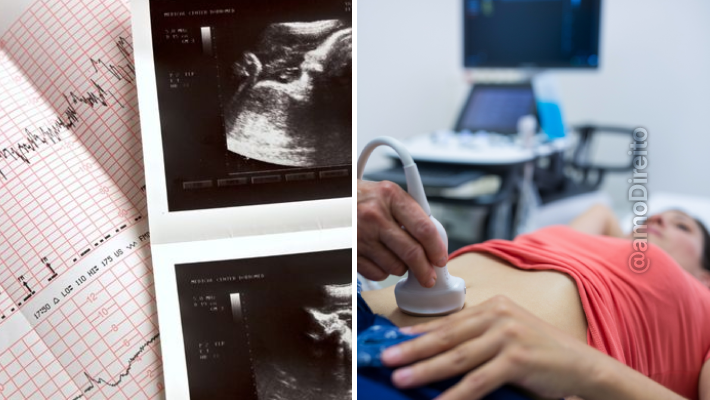

O trecho mais polêmico da lei, sancionada na última quinta-feira (11/1), diz que o Estado deve fornecer o exame de ultrassom contendo os batimentos cardíacos do nascituro para a mãe. A lei nº 22.537/2024 entrou em vigor na data da publicação, mas o texto não deixa claro a partir de quando os hospitais vão começar a obrigar as grávidas a ouvir o coração do feto, informando que a medida será fornecida “assim que possível”.